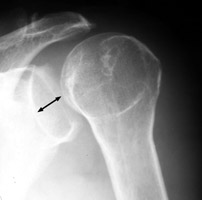

Posterior shoulder dislocation

AP radiograph reveals apparent increase in space between the anterior rim of the glenoid fossa and the medial aspect of the humeral head. This is termed the "positive rim sign." It may be present in posterior dislocation because the normal glenoid fossa faces as much anteriorly as it does laterally. Since the dislocated humeral head rests against the posterior glenoid rim, the space between the anterior rim and the humeral head appears increased.

Shoulder posterior dislocation - Click on the image for a larger version